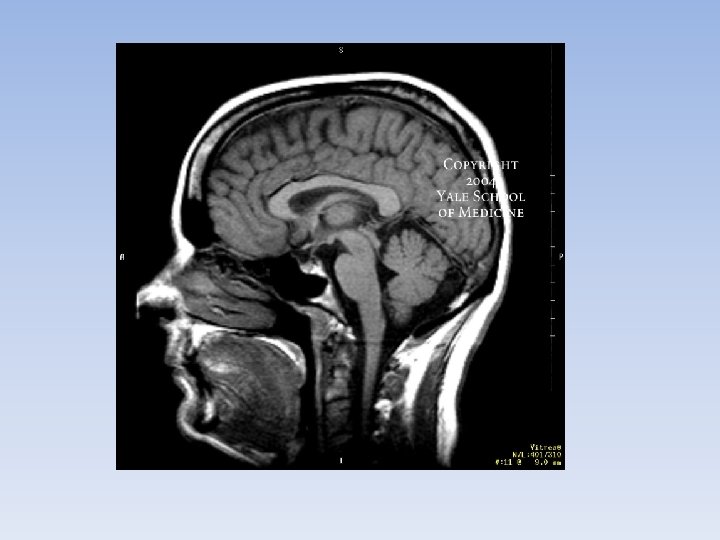

Positron Emission Tomography • Nuclear medicine that uses radioisotopes that emit particles called positrons. • Usually used to detect cancer in tissues, heart disease and some brain disorders such as Alzheimer’s disease.

Biophotonics • Light is shone on cells and tissues. The light is scattered by the molecules of the cells and a special device is used to record these scatter patterns. • This produces an image. • Doctors can things like endoscopes to examine deep inside the body. An endoscope is a thin tube with a bright light and a camera.